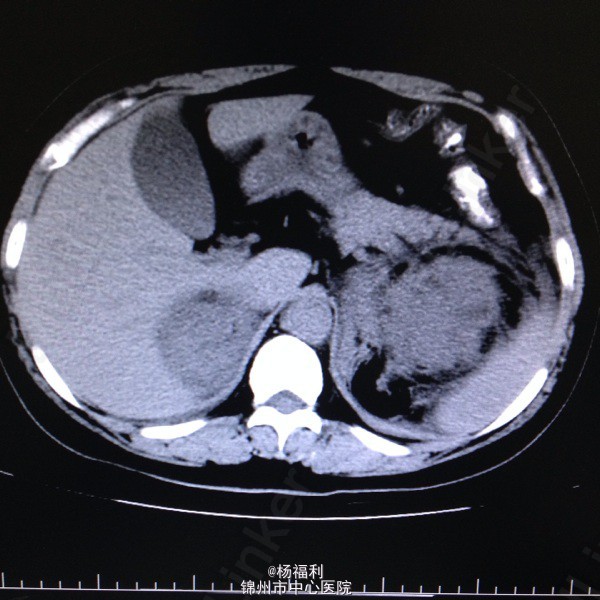

44岁女患。为消化科我会诊患者。 现病史:以上腹痛9小时为主诉入院。无发热及寒战、噁心未呕吐,无腹泻及黑便。 既往史:双眶炎性假瘤2年,口服激素治疗,并补钾。

查体:上腹部压痛,无反跳痛、右侧压痛明显,右肾区叩击痛,左肾区轻叩击痛,双输尿管走形区无压痛。 辅助检查;泌尿系彩超:双肾积水。 血白细胞:9.99*10^9。 肾功能正常。 全腹部ct及MRU检查:见图片。

诊断;真的不知道是啥病。 处理:暂时止痛处理。双肾病变。不知从哪里下手。